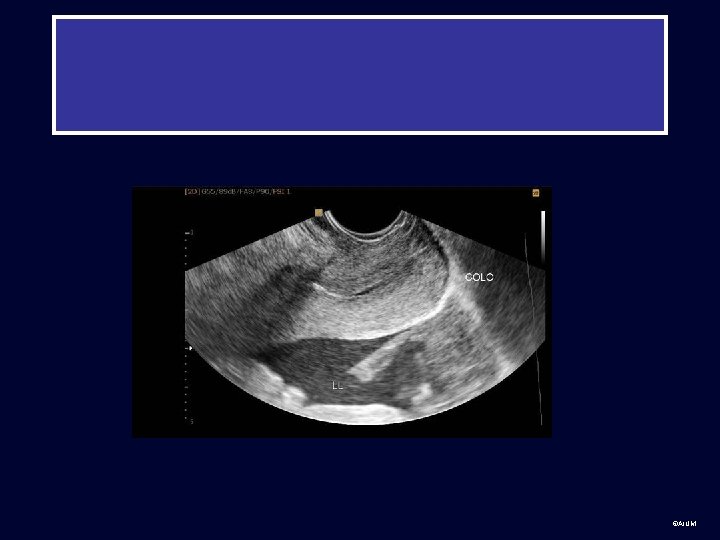

Second Trimester Placenta and cervix: placenta previa • Placenta ©AIUM